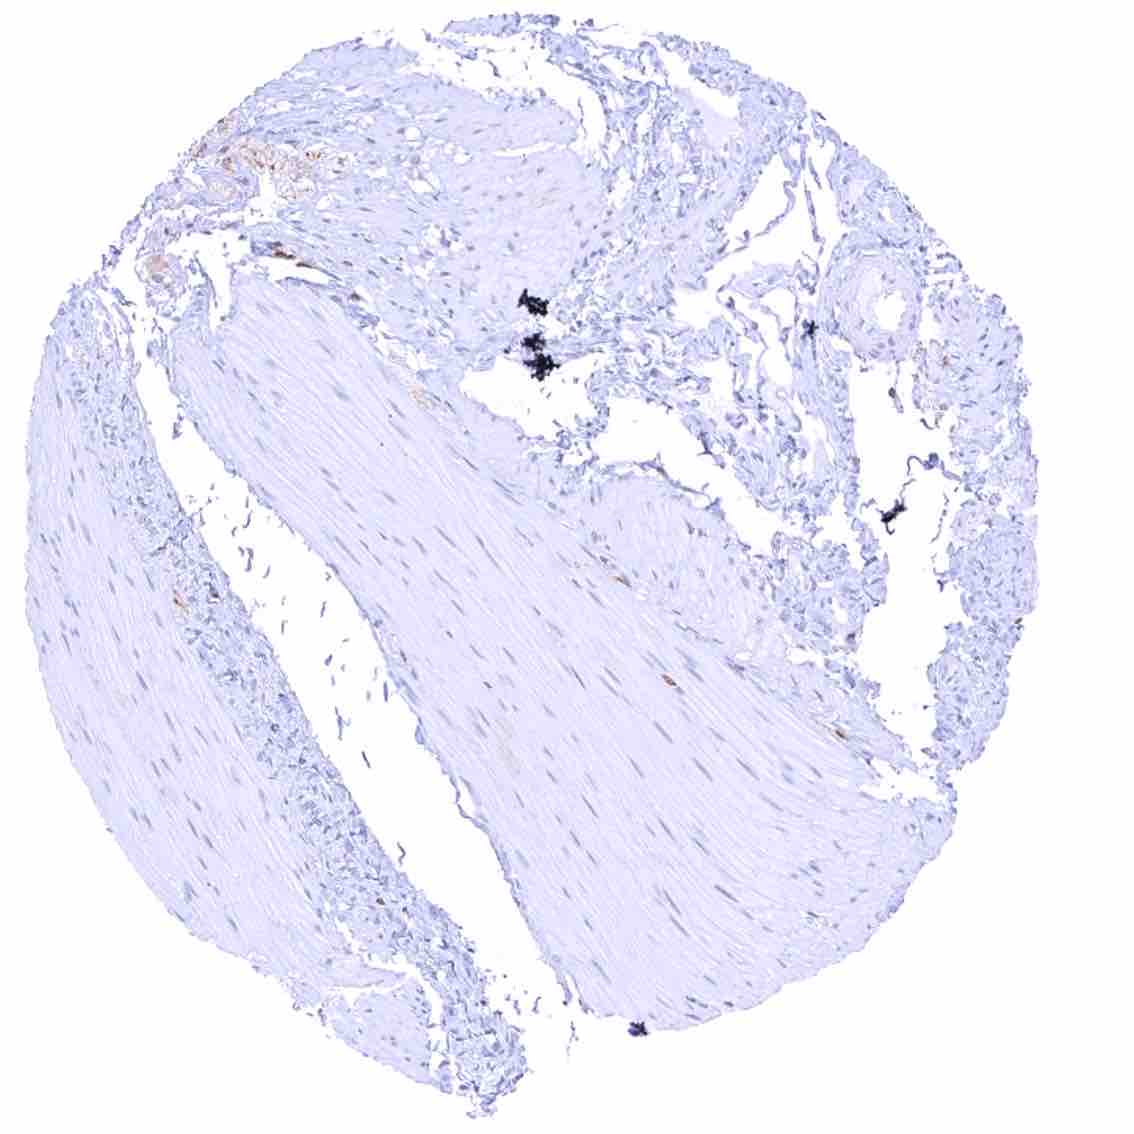

Urinary bladder, muscular wall